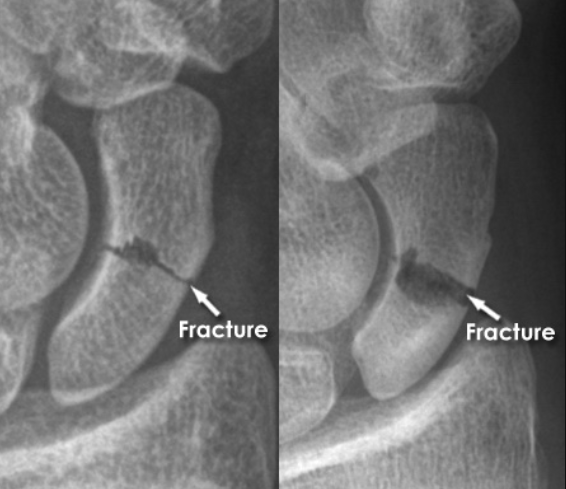

- 먼저 방사선 손목 사진을 찍어서 확인합니다. 그러나, 처음 방사선사진에서 나타나지 않더라도 골절이 의심되면 2-3주 후에 다시 찍어 재확인하여야 합니다. 필요한 경우에는 뼈스캔(bone scan), CT, MRI 등의 특수 검사를 하여 확인해야 합니다.

- 잘 확인이 되지 않았을 때 엑스레이를 반복했을 때 골절부위가 벌어진 타이밍에 관찰될 수 있기 때문입니다.

- 아래 엑스레이처럼 잘 관찰해야 보입니다.